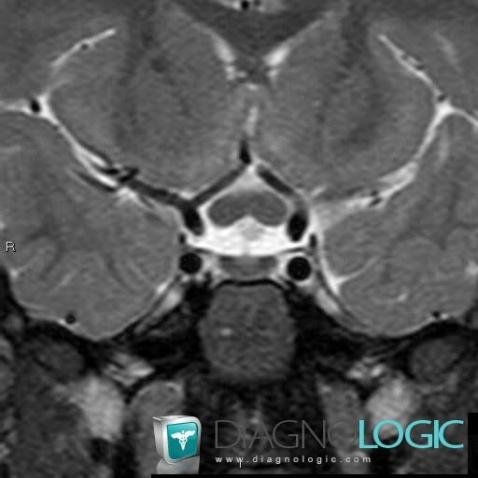

Gliome-nerf optique , OEil, IRM

Voici les informations spécifiques à l'image clé ci dessus:

- Diagnostic Gliome du nerf optique , Localisation(s) Oeil, comportant les gammes Lésion du nerf optique